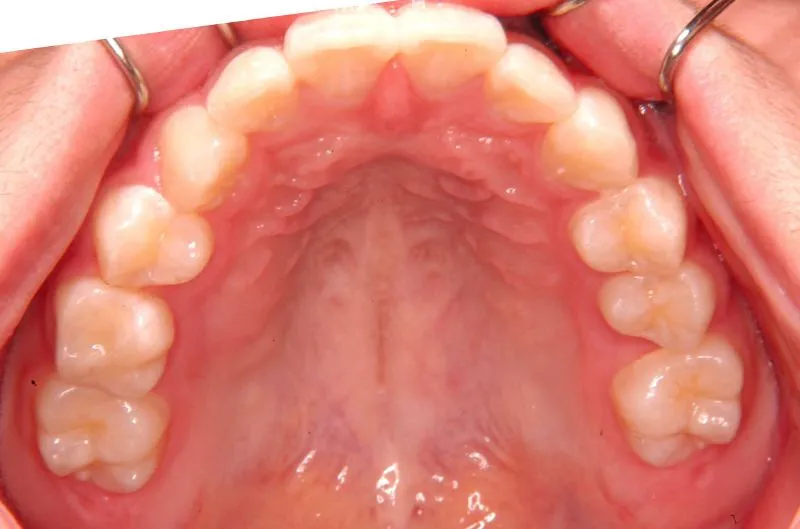

初診時年齢 小学校6年生 (女性) 主訴 犬歯がずれている・噛み合わない

診断名 叢生・交叉咬合 装置名

右下の犬歯がずれて生え噛み合わせの邪魔をしています。

歯は抜かず、上下マルチブラケット装置を使用し治療いたしました。

治療回数54回、9年3ヶ月の治療期間で矯正治療を終了しました。